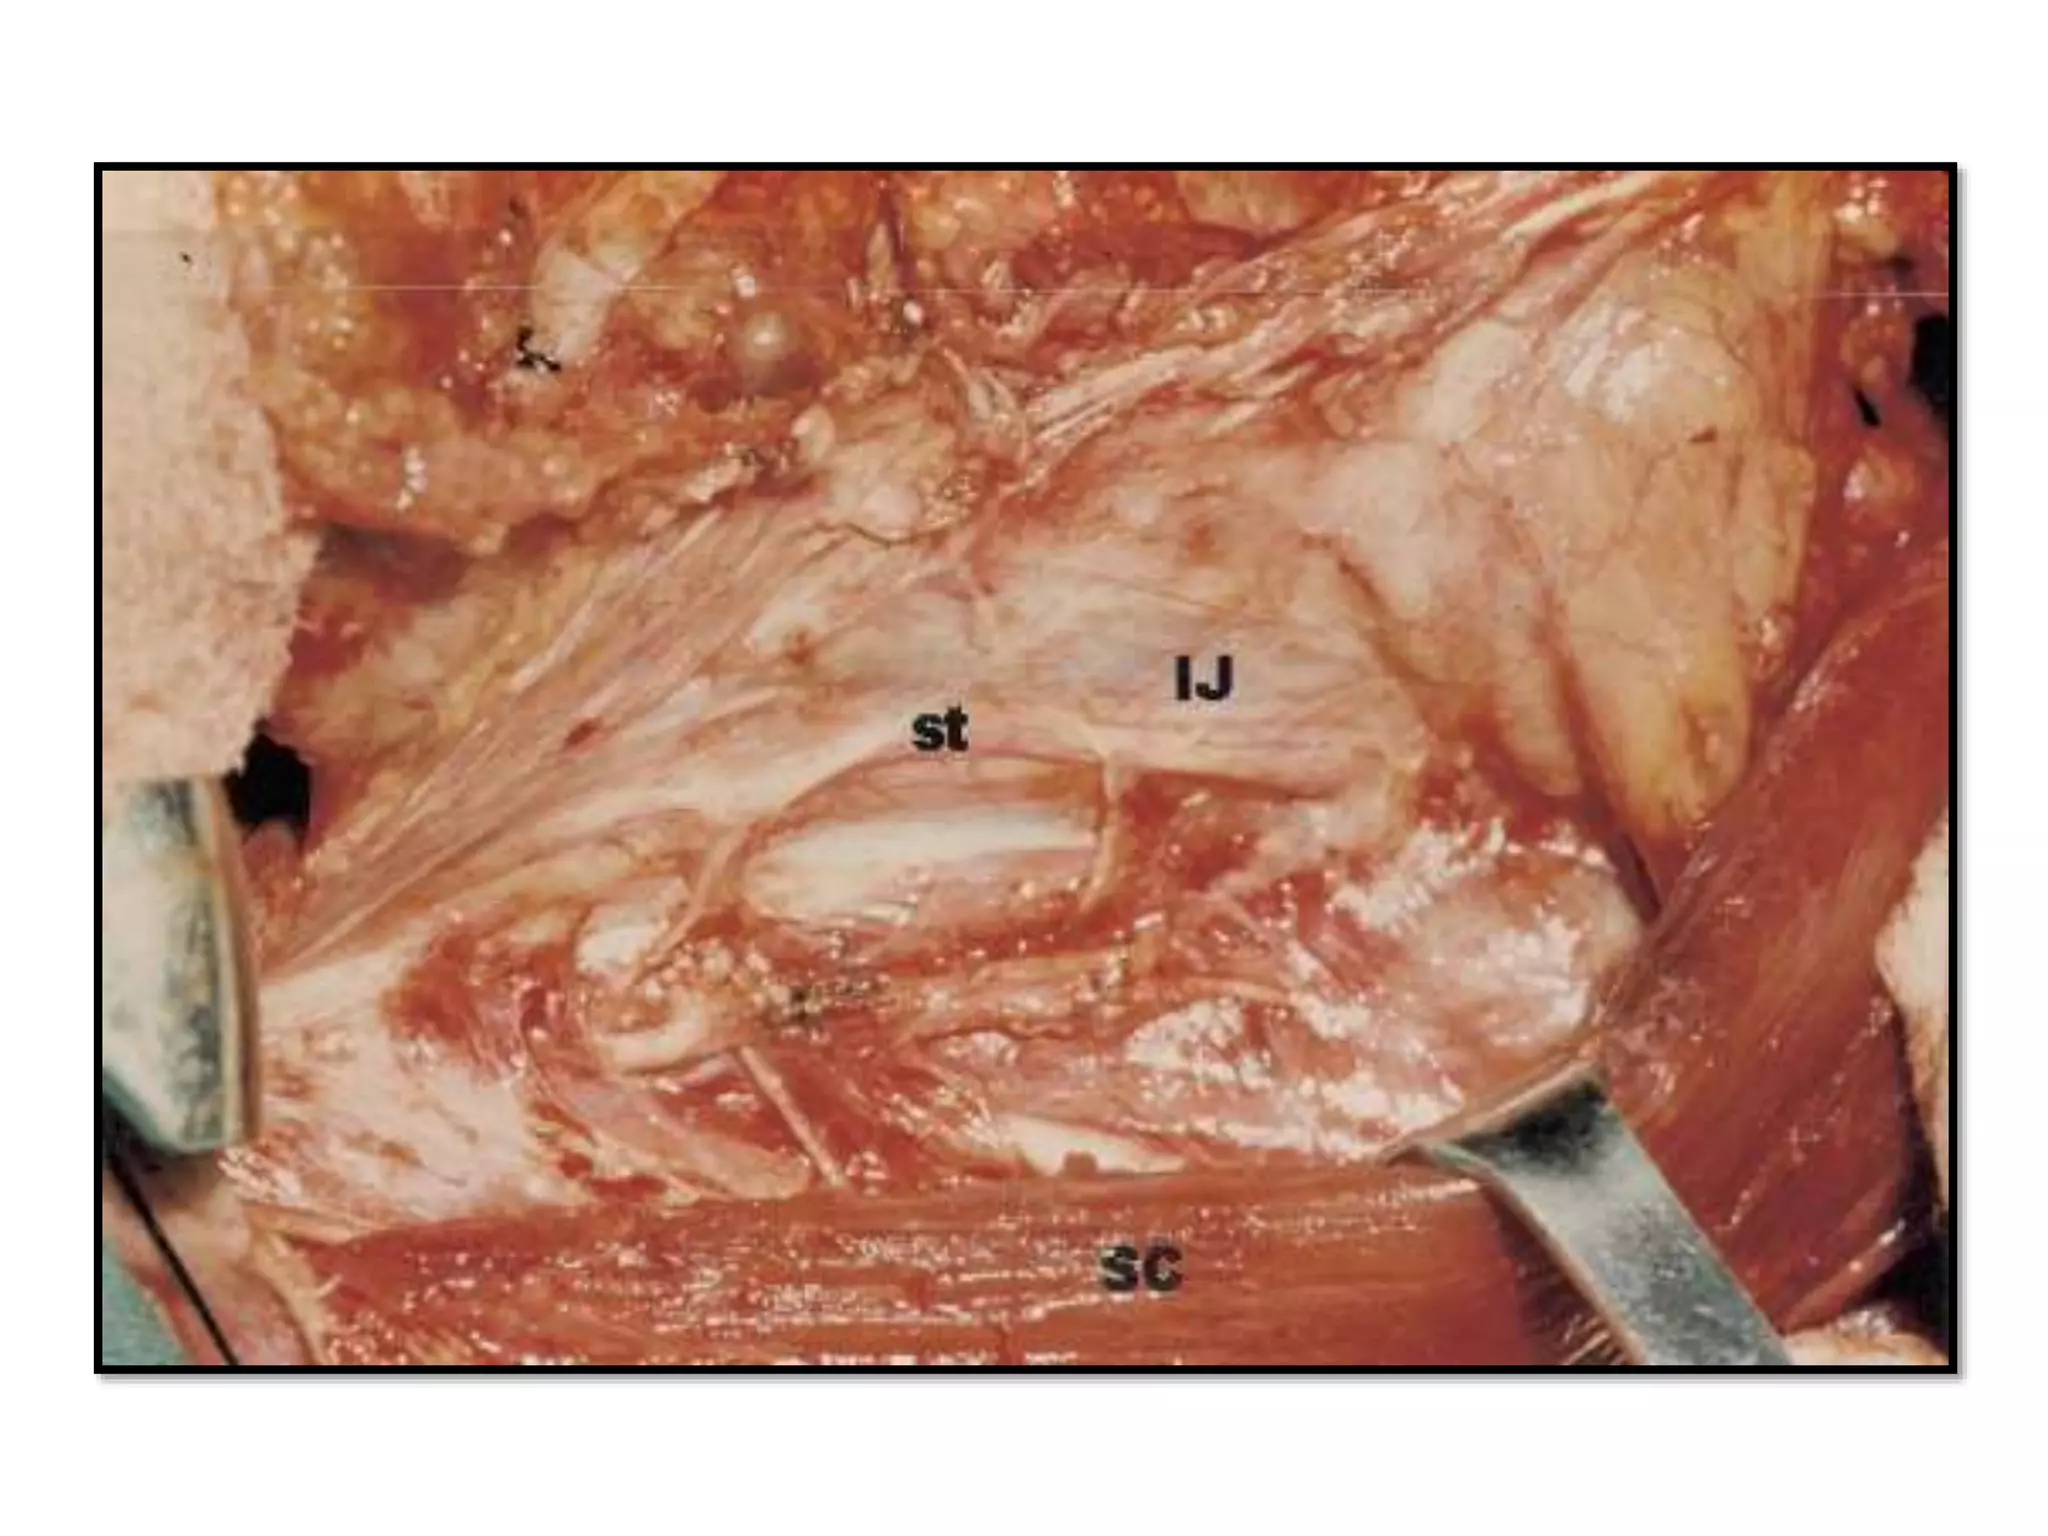

• #96 The spinal accessory maneuver has been completed. A final cut is made anterior to the sternocleidomastoid muscle (- - - - - - - -), between the spinal accessory nerve and the level of Erb’s point (right side). SC, sternocleidomastoid muscle retracted posteriorly; sa, spinal accessory nerve; S, specimen from the upper jugular and spinal accessory area. a final cut is made in this area that will help further dissection

• #110 Artist’s view of the neck after right functional neck dissection. IJ, internal jugular vein; fv, distal stump of the facial vein; CA, carotid artery; st, superior thyroid artery; SG, submandibular gland; PG, parotid gland; TG, thyroid gland; oh, omohyoid muscle; sh, sternohyoid muscle; dm, digastric muscle; sp, splenius capitis muscle; ls, levator scapulae muscle; as, anterior scalene muscle; SC, sternocleidomastoid muscle; sa, spinal accessory nerve; vn, vagus nerve; pn, phrenic nerve; hn, hypoglossal nerve; BP, brachial plexus; tc, transverse cervical artery; , deep branches of the cervical plexus.